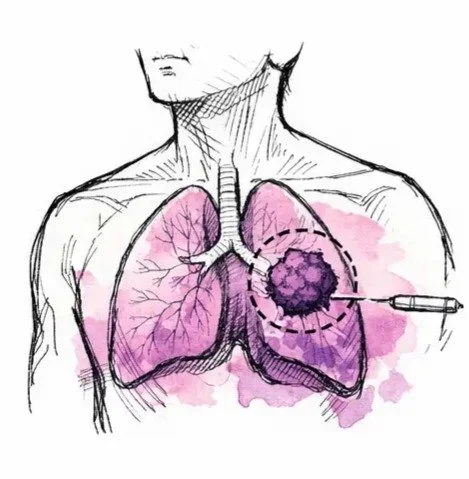

Biopsi

1.

Platin-DRP® utförs med hjälp av den redan tillgängliga FFPE-tumörbiopsi som tas inom rutinpatologi. Ingen ytterligare procedur krävs, vilket gör processen icke-invasiv och fullt integrerad i befintliga kliniska arbetsflöden. Från biopsi till resultat är svarstiden cirka 72 timmar.